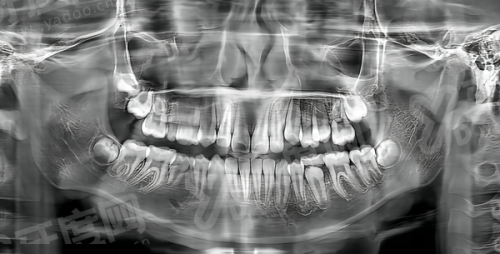

北京倪氏口腔倪以亮是采用3D口腔扫描技术,能够快速精细获取患者口腔内牙齿、牙槽骨等结构的三维数据,避免传统取模带来的不适感,数据精度高,为方案设计提供可靠依据;通过计算机辅助设计软件,模拟矫正过程及更终效 果,让患者提前直观了解矫正后的牙齿状态,增强患者对治疗的信心,同时便于医生与患者沟通方案细节;根据患者的牙齿数据和矫正目标,精细计算牙齿移动轨迹,制定个性化的矫正方案,确保矫正过程科学有序,提高矫正效率和效 果。

北京倪氏口腔倪以亮在隐形矫正过程中,能够根据患者牙齿移动情况及时调整矫治器,对于复杂病例,可通过分步设计矫治器,实现牙齿的精细移动,达到理想的矫正效 果;是注重咬合关系的调整,不仅关注牙齿排列整齐,还重视上下颌牙齿的咬合功能,确保矫正后牙齿既能美观又能正常行使咀嚼功能;对于隐形矫正过程中可能出现的牙齿脱轨等问题,能够及时发现并采取有效措施进行处理,保护矫正过程顺利进行。

北京倪氏口腔倪以亮对于成人骨性错颌畸形患者,能够结合正畸-正颌联合治疗的理念,与颌面外科医生协作,制定综合治疗方案,帮助患者改善面部轮廓和咬合关系;北京倪氏口腔倪以亮在青少年生长发育高峰期,能够抓住矫正的黄金时期,通过功能矫治器等手段引导颌骨正常发育,预防错颌畸形的进一步发展,取得较好的治疗效 果;北京倪氏口腔倪以亮对于二次矫正患者,能够分析首次矫正失败的原因,制定针对性的矫正方案,解决牙齿复发、咬合不良等问题,帮助患者重新获得整齐的牙齿。